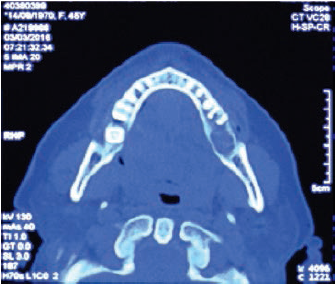

Clínicamente, se evidenciaba una deformidad en el contorno de la región del ángulo mandibular izquierdo. Intraoralmente, se observaba una lesión tumoral de 2,5 cm de alto por 2,7 cm de diámetro. Tomográficamente, estaba registrada una imagen hipodensa en la zona del segundo molar inferior izquierdo, con una expansión de cortical a vestibular y lingual ipsilateral (figuras 2 y 3). Radiográficamente, en la zona periapical del segundo molar inferior izquierdo, se observó un ensanchamiento del espacio del ligamento periodontal, sin causa aparente, con pérdida ósea perirradicular (figura 1). La paciente refirió que un año atrás, aproximadamente, se le había realizado una exodoncia del tercer molar inferior izquierdo, sin complicaciones, concomitante con el crecimiento de dicha lesión. Posterior a la evaluación, los servicios de Cirugía Plástica, Maxilofacial, Cabeza y Cuello realizaron una junta médica, donde se tomó la decisión de llevar a cabo una mandibulectomía segmentaria con reconstrucción de colgajo microvascularizado de cresta iliaca y vaciamiento ganglionar cervical ipsilateral.